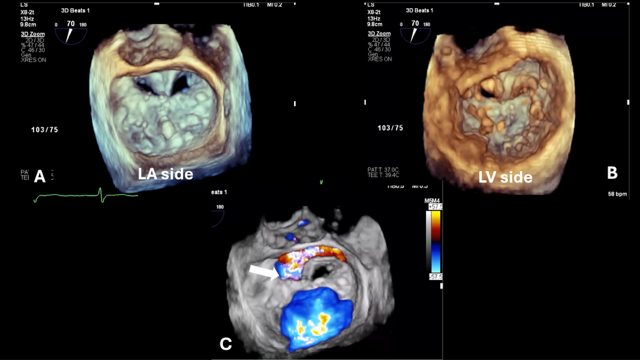

Transthoracic echocardiogram showed severe MR and transesophageal echocardiogram (TEE) showed the Alfieri stitch located at A2/P2 with the tip of the anterior mitral valve leaflet sutured to the ventricular side of the posterior annulus. The origin of the MR was just lateral to the stitch with the Coandă effect into the left atrium; the Coandă effect refers to the wrapping of the eccentric mitral regurgitant jet around the atrial wall by color Doppler (Figure 1). Due to the complicated repair and residual leaflet billowing, determination of the regurgitant jet origin by 2-dimensional TEE was challenging. Multiplanar reconstruction (MPR) of the 3-dimensional (3D) TEE images was used to sweep through the valve, measure leaflet lengths at specific valve segments, and confirm the origin of the MR jet in the challenging post-repair valve anatomy (Figure 2). The mitral valve area (4.0 cm2) was also directly measured using MPR (Figure 3). The patient was determined to be high surgical risk for redo mitral valve surgery (STS score 16.8%) and was referred for mitral edge-to-edge repair.